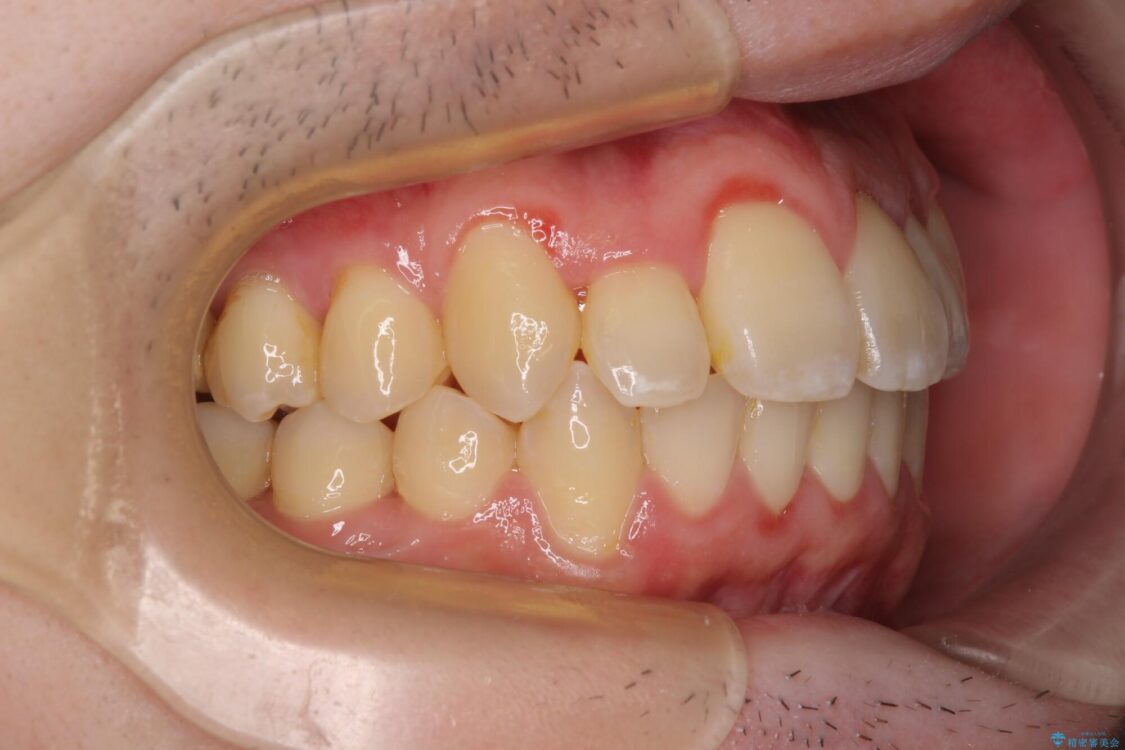

八重歯や奥歯の噛みにくさを気にして来院された患者様です。

前歯のクロスバイトや八重歯の他に、左右最後臼歯のシザーズバイト(鋏状咬合)が認められました。

治療前

• 全顎的なクロスバイト 補助装置を用いてワイヤー矯正 治療前画像